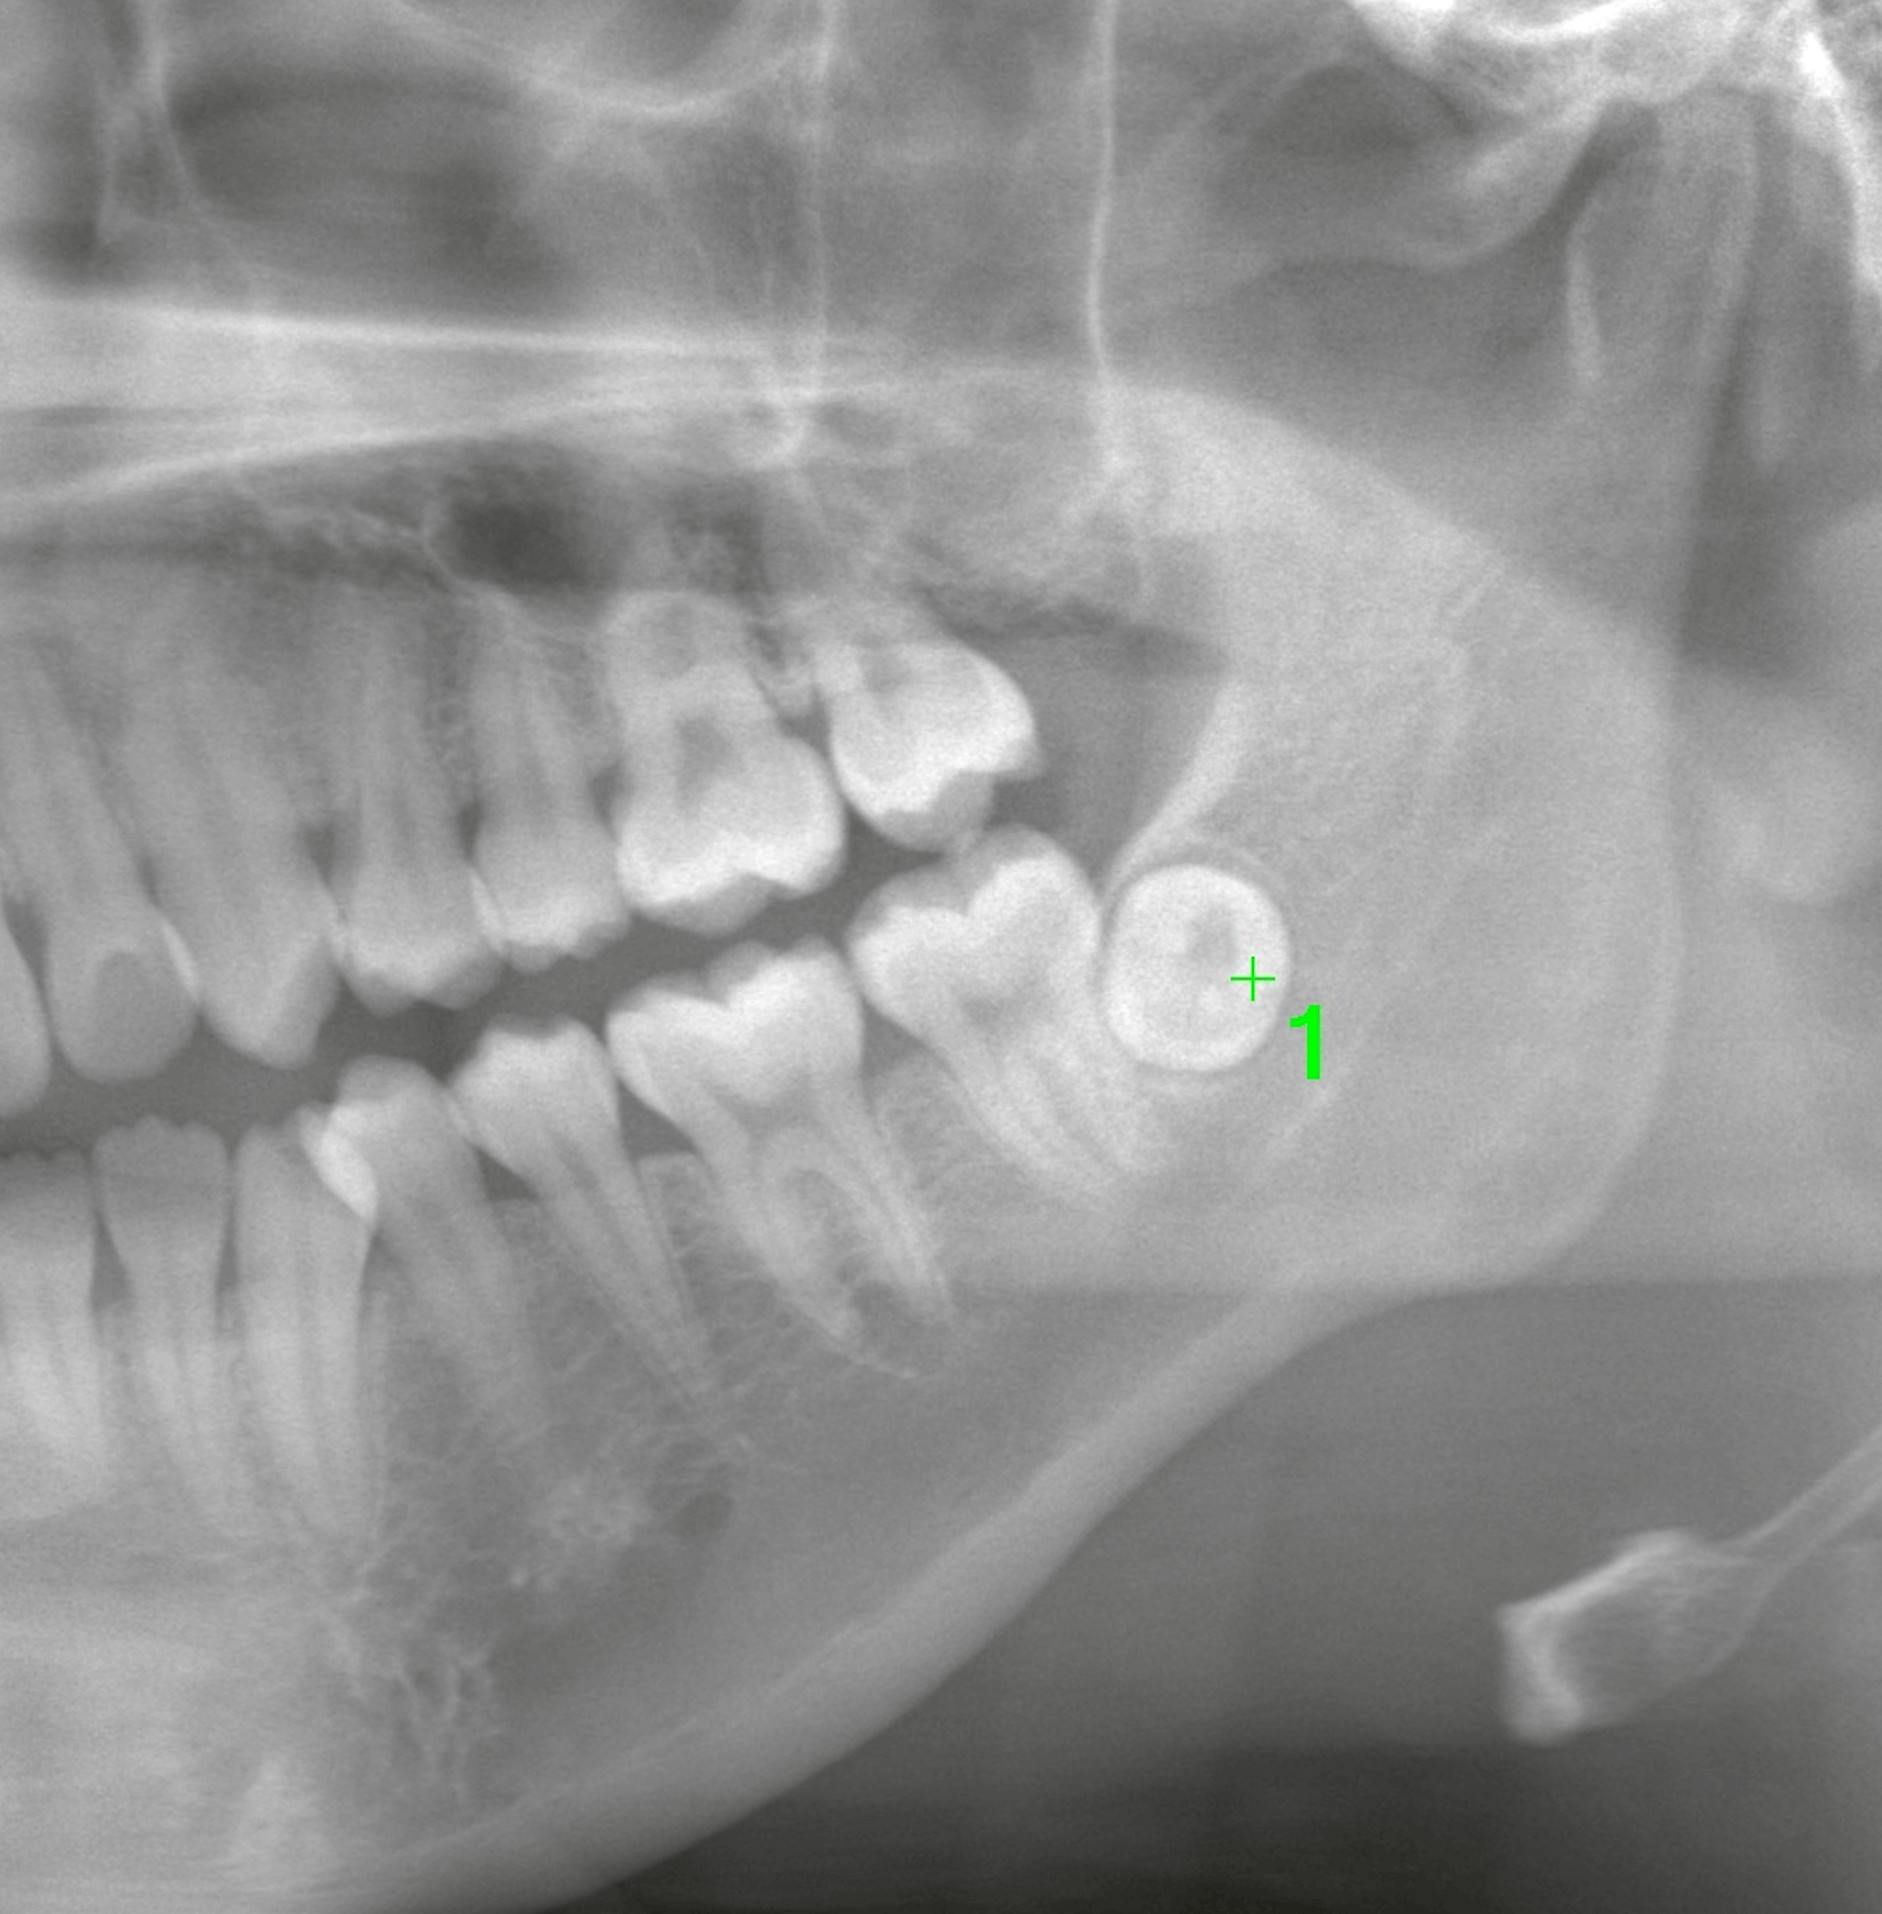

まずはパノラマレントゲンを撮影。

レントゲン上では、左下の親知らずが「まん丸」に映っています。

しかし今回の写り方は明らかに違う。

「歯根が見えない?」

この丸く見える像は、頬舌的(左右方向)に傾斜している可能性を示唆します。

つまり

・歯冠が舌側

・歯根が頬側

あるいはその逆。

パノラマでは確定できません。